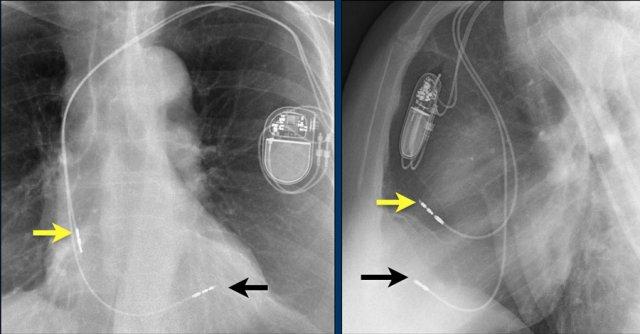

Hội chứng Twiddler

Hình ảnh bên trái cho thấy bệnh nhân có ICD được đặt đúng vị trí.

Vài tháng sau, thiết bị hoạt động không bình thường do hộp ICD và điện cực bị xoay (mũi tên vàng) và co rút lại (mũi tên trắng).

Đây là một bệnh nhân khác mắc hội chứng Twiddler.

Lưu ý hình ảnh điện cực bị cuộn xoắn gần máy tạo nhịp và tại đầu điện cực trong thất phải (mũi tên).